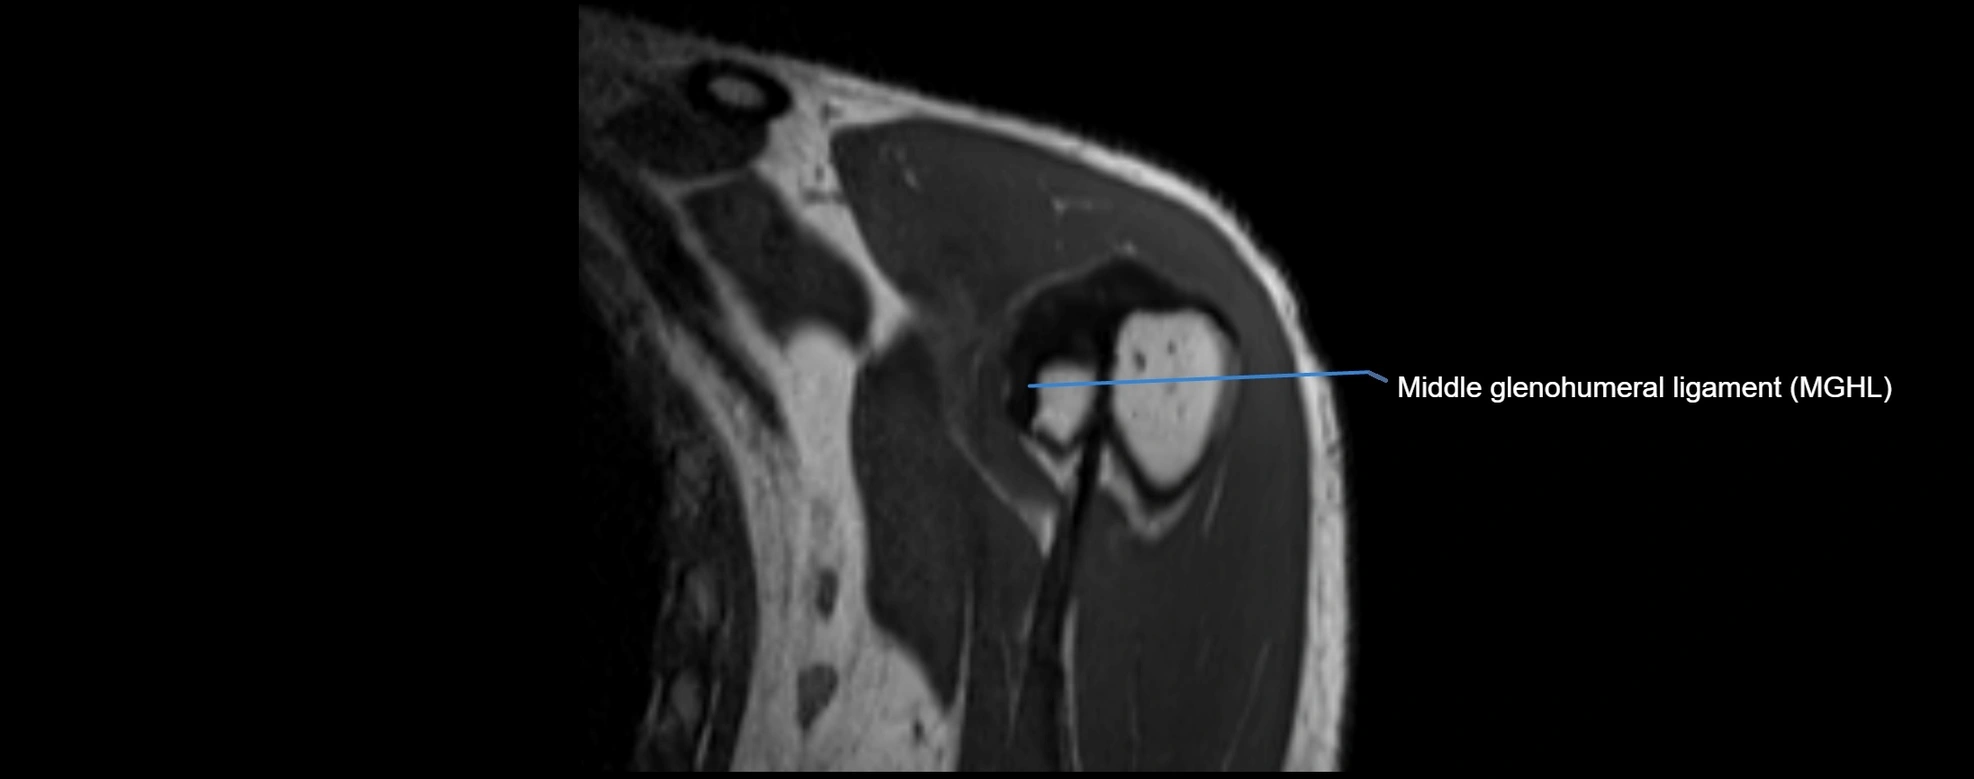

MRI images

image